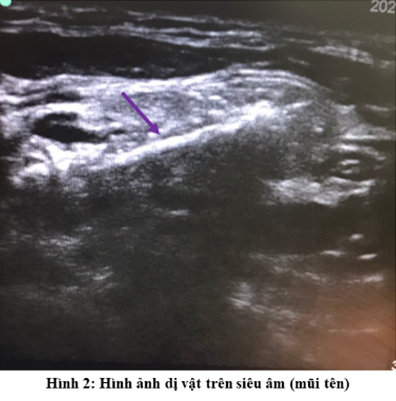

Khi lỗ thủng được gây ra bởi dị vật, thì loại bỏ dị vật phải được thực hiện ngay lập tức. Nếu dị vật không được phát hiện trong quá trình phẫu thuật, siêu âm nên là phương tiện đầu tiên được xem xét để định hướng vị trí dị vật.

Bệnh nhân được phẫu thuật nội soi thực quản ống cứng để lấy dị vật, tuy nhiên, không phát hiện dị vật trong lòng TQ. Bênh nhân được thực hiện xét nghiệm bổ sung bao gồm siêu âm, CT scan và đã phát hiện dị vật đã di chuyển ra tam giác cổ sau. Thêm vào đó, trên đường di chuyển của mình dị vật để lại hình ảnh dò các bóng khí từ TQ đến ổ thâm nhiễm có dị vật cản quang.

Bệnh nhân đến lúc này được phẫu thuật cấp cứu mở cạnh cổ lấy dị vật, trong quá trình phẫu thuật với sự trợ giúp của siêu âm đã lấy ra được dị vật là một mảnh xương cá đường kính 2 mm, chiều dài 20 mm. Thám sát đường dò đến tận TQ hút được khoảng 10 ml dịch mủ trắng đục và tiến hành súc rửa đường dò bằng betadin. Sau đó dẫn lưu qua da đường dò và đóng vết mổ. Hậu phẫu ngày thứ 3 tiến hành để hở vết mổ 1/3 dưới mục đích chăm sóc và dẫn lưu đường dò. Bệnh nhân được xuất viện một tuần sau đó với tình trạng ổn định và sẽ được đóng đường dò thì hai sau đó.